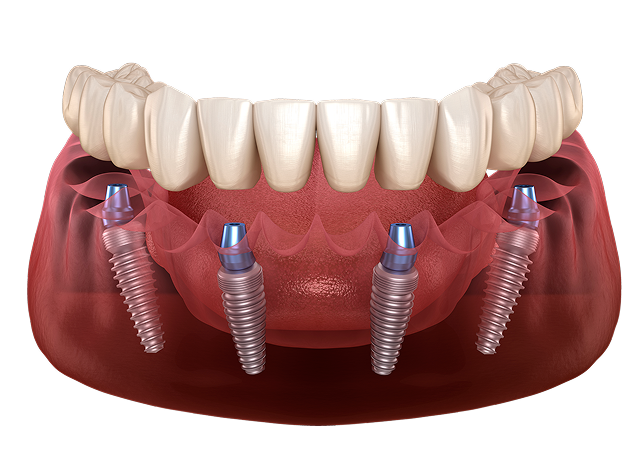

Сколько имплантов надо ставить на одну челюсть?

4 импланта

• Минимальное количество имплантов

• Бюджетный план лечения

• Без костной пластики

Стоимость под ключ 300 000 ₽